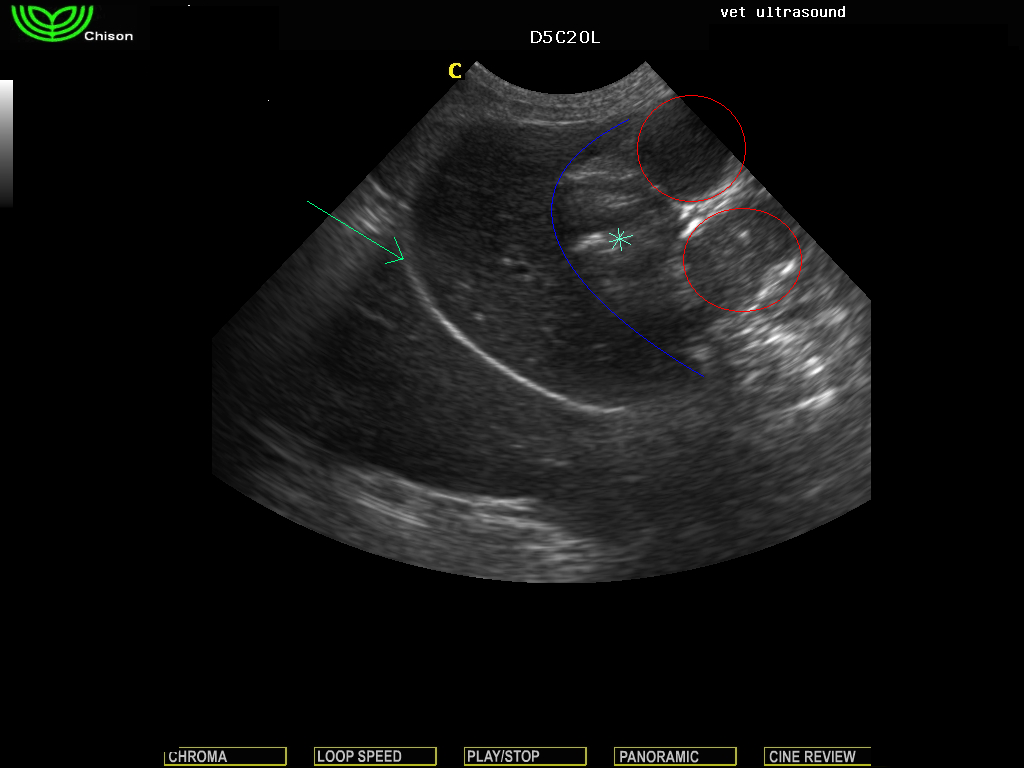

πράσινο βέλος διάφραγμα, η μπλέ γραμμή αφορίζει το ήπαρ, ο αστερίσκος δείχνει το στομάχι, οι κύκλοι περιβάλουν το διατεταμένο λεπτό έντερο.